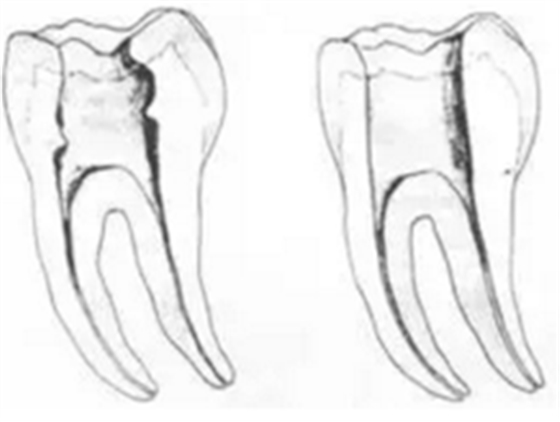

二、根管預(yù)備后形態(tài)

牙體缺損的修復(fù)需要將剩余牙體組織制備成一定形態(tài),以利修復(fù)體的良好固位。根管充填為了致密封閉根管系統(tǒng)也需要良好的根管預(yù)備后形態(tài)。

三、開髓孔

1. 正常開髓孔的位置和大小

左圖為正常開髓孔的大小和位置。左邊圖為下顎,右邊圖為上顎。

2. 根管治療中開髓孔的設(shè)計標(biāo)準(zhǔn)

根管治療需去除髓腔內(nèi)容物(去除髓室頂),建立所有根管的入路,允許沖洗液大量沖洗。開髓孔的設(shè)計標(biāo)準(zhǔn)以建立通路為目的,從而建立良好的視野和術(shù)野。

( 1 )直線通路:根管治療時需要一個直線通路,直線通路能夠達(dá)到根尖三分之一

測量標(biāo)準(zhǔn):以允許根管器械直線并直接進(jìn)入根尖 1/3 且不接觸冠方各壁為標(biāo)準(zhǔn)。

( 2 )髓腔其他改變:如髓室頂、繼發(fā)性牙本質(zhì)、修復(fù)性或增齡性牙本質(zhì)。見左圖。

右圖中有繼發(fā)性牙本質(zhì),切削后獲得直線通路。

四、根管預(yù)備步驟

根管預(yù)備步驟包括:

( 1 )橡皮障的使用。

( 2 )X片共四張 (術(shù)前、診斷絲 、主牙膠尖確認(rèn)、術(shù)后)。

( 3 )開髓、確認(rèn)工作長度( WL )。全程疏通到 20 號(從 08K-10K 、 H-15K 、 H-20K )。

( 4 )根管上段(冠方 1/3—1/2 )的預(yù)備。

( 5 )根管中段(距狹窄部 2mm 以上)的預(yù)備。

( 6 )根管下段(狹窄部 2m)